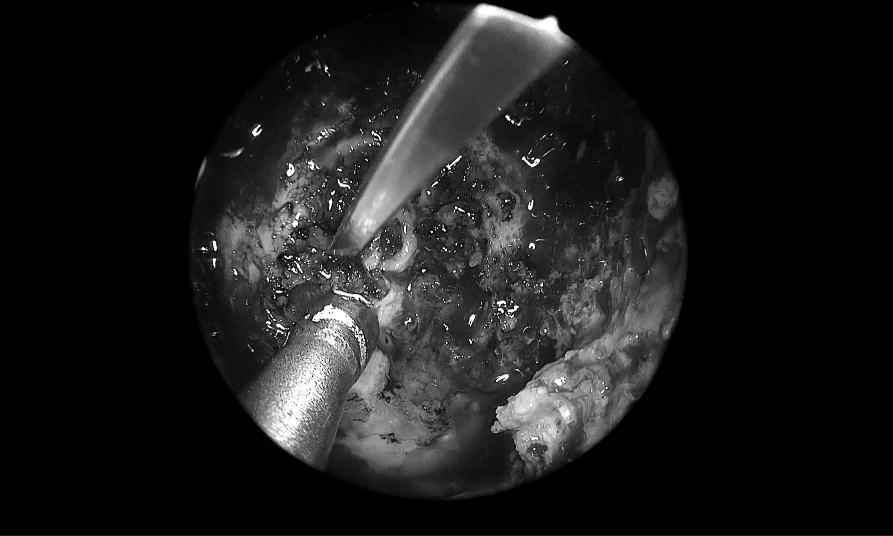

取出部分腫瘤,進(jìn)行瘤內(nèi)減壓